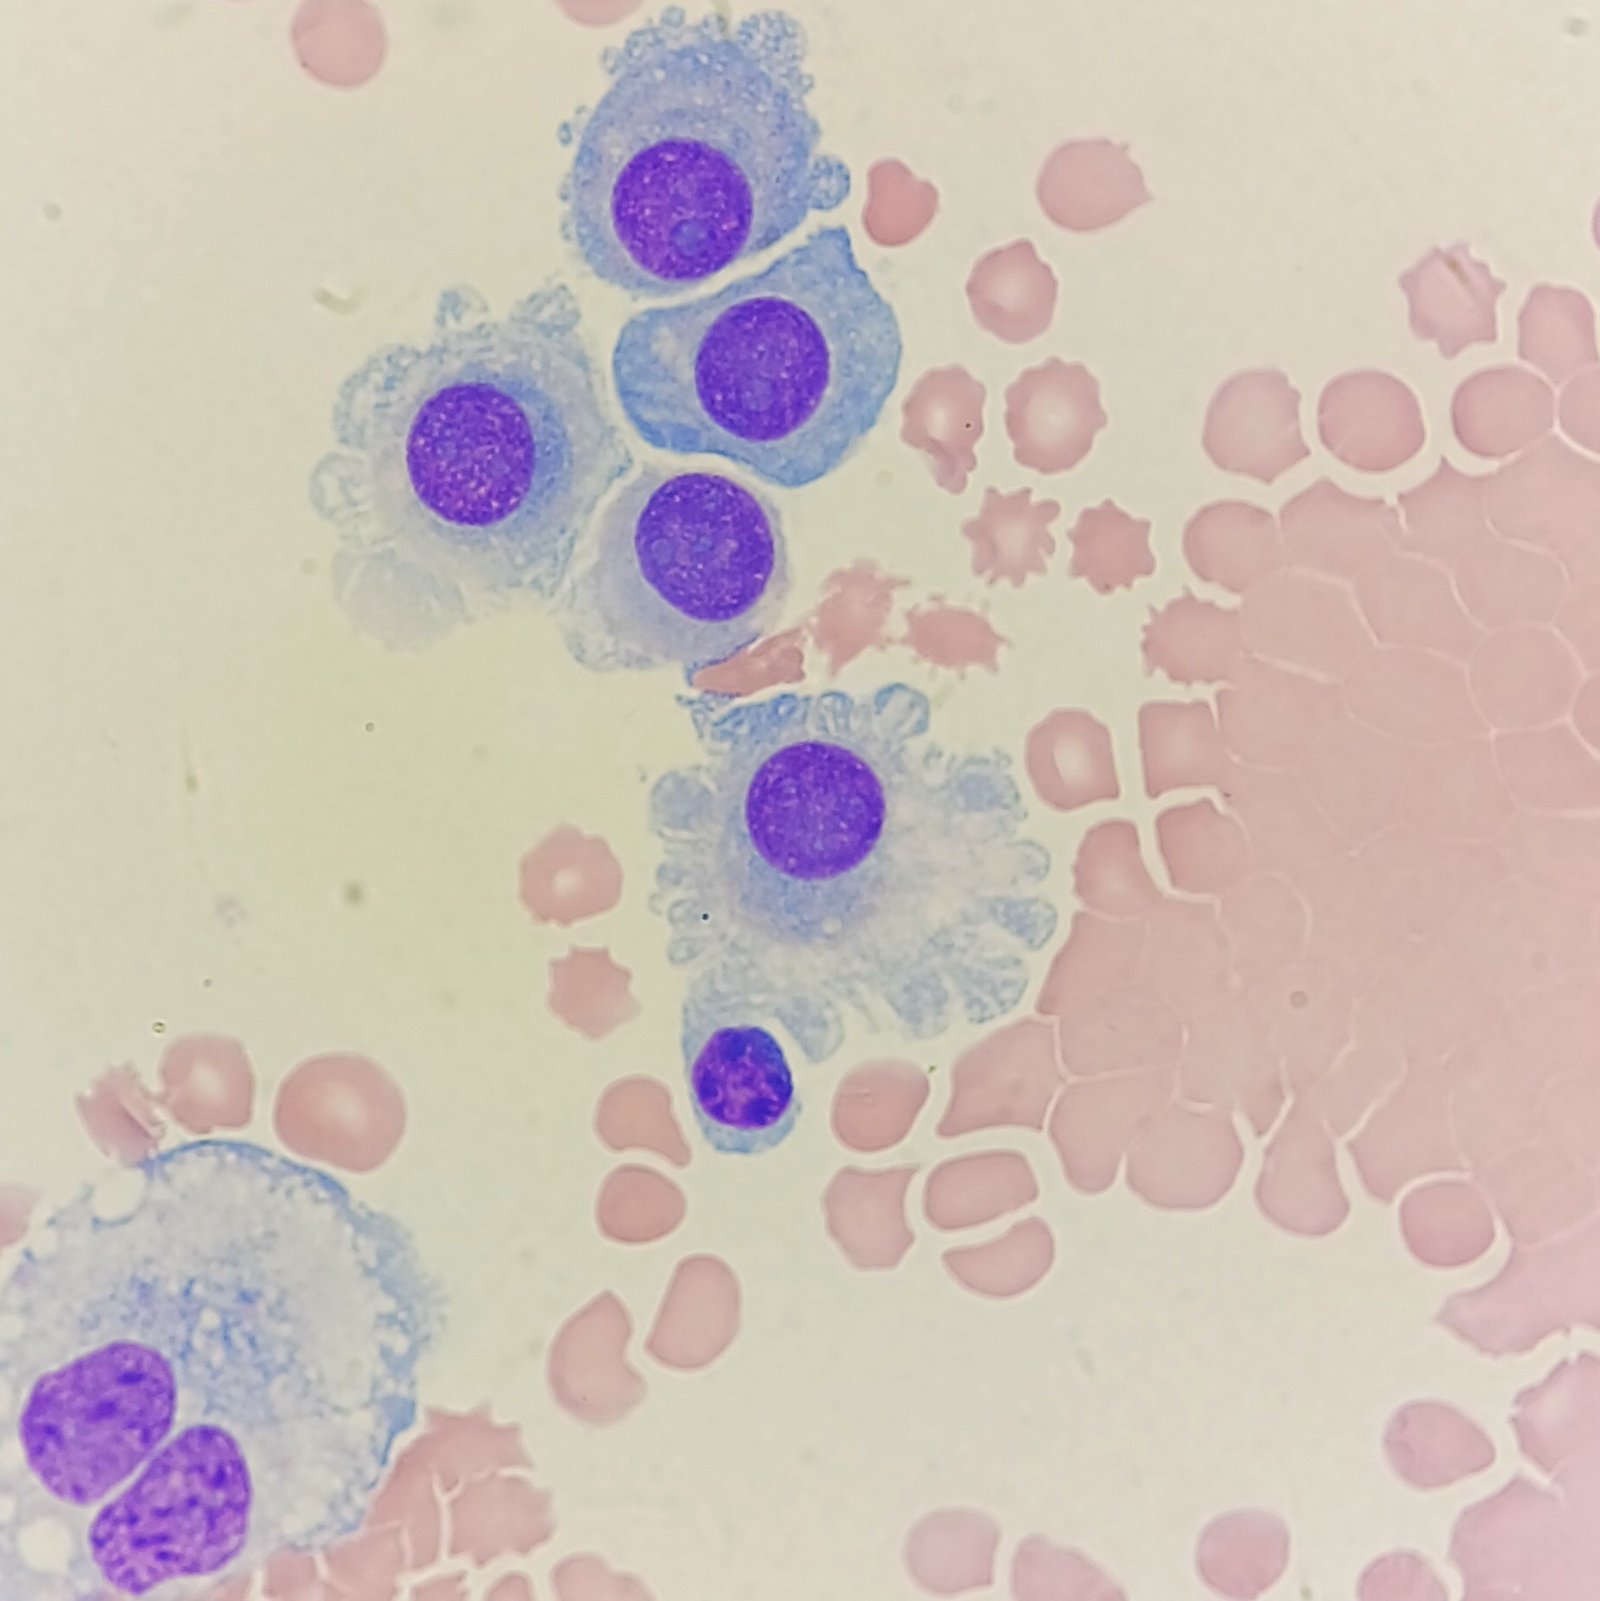

Mesothelial cells are described as having a “fried egg” appearance. They have a round to oval nucleus with smooth borders and evenly distributed chromatin. Nucleloli are usually present. Mesothelial cells may also be multinucleated.

Cells may be seen in clumps, but “windows” between cells still allows for individual counting.

Macrophages are about the same size as mesothelial cells, so the two can often be confused. Macrophages can usually be differentiated by the presence of vacuoles and a lacey chromatin. If both cell types are present and differentiation is difficult, take a look around the slide to get an idea of each kind of morphology before starting a differential.